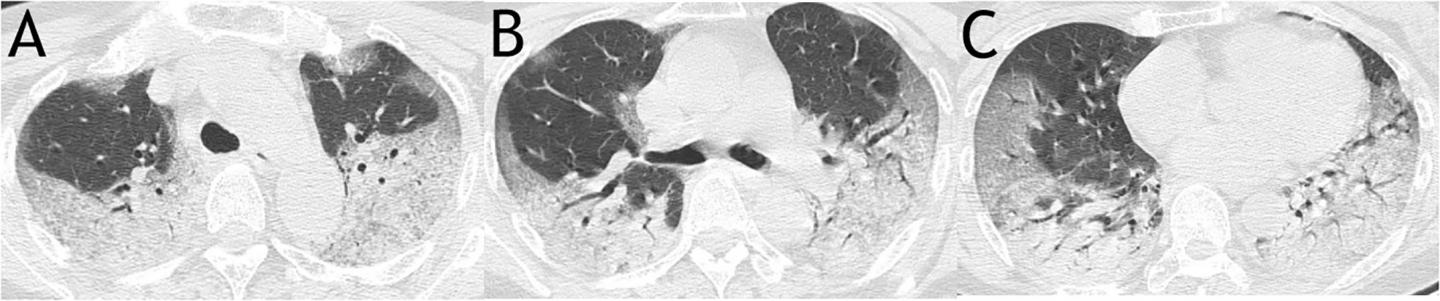

image: Fig 1. A sample scoring on CT images of a 63-year-old woman from mortality group demonstrated a total score of 63.

It was calculated as: for upper zone (A), 3 (consolidation) × 3 (50-75% distribution) × 2 (both right and left lungs) + 2 (ground glass opacity) ×1 (

In this patient group, the authors associated clinical features identified from computed tomography (CT) scans of patients' lungs with eventual outcomes. They scored patients based on features they observed such as ground glass opacity, abnormality on both sides, and widespread distribution of pathology in the lungs, to produce an overall severity score for each patient.

Of the 27 patients, who were mostly older adults (median age 60), 17 (63 percent) recovered and were discharged from hospital, while 10 (37 percent) died of the virus. Patients with underlying health conditions including hypertension, diabetes and cardiac disease were more likely to die of the virus than patients without such comorbidities, and older patients were also more likely to die, though there was no difference between genders. Patients with a higher (more severe) score at CT scan were much more likely to die of COVID-19 - the average score of patients who died was 30, compared to 12 in patients who recovered.